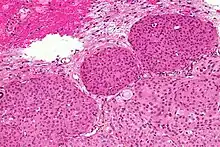

Pathophysiology

- A woven architectural pattern

- Psammoma bodies (spheroid calcifications)

- Syncytial cells (having indistinct cell membranes) with eosinophilic (pink) cytoplasms

- Round uniform nuclei

- Whorls (concentric cell arrangements)[15]

Meningiomas arise from arachnoidal cap cells,[16] most of which are near the vicinity of the venous sinuses, and this is the site of greatest prevalence for meningioma formation. Some subtypes may arise from the pial cap cells that migrate during the development together with blood vessels into the brain parenchyma.[17] They most frequently are attached to the dura over the superior parasagittal surface of frontal and parietal lobes, along the sphenoid ridge, in the olfactory grooves, the sylvian region, superior cerebellum along the falx cerebri, cerebellopontine angle, and the spinal cord. The tumor is usually gray, well-circumscribed, and takes on the form of the space it occupies. They usually are dome-shaped, with the base lying on the dura.

Histologically, meningioma cells are relatively uniform, with a tendency to encircle one another, forming whorls and psammoma bodies (laminated calcific concretions).[18] As such, they also have a tendency to calcify and are highly vascularized.